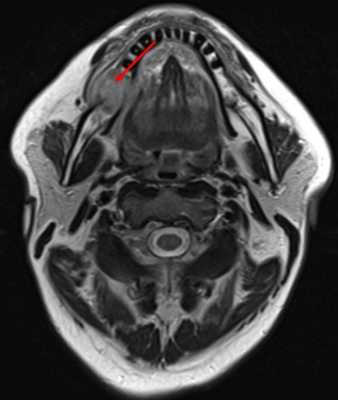

- КТ, МРТ с контрастным усилением или без (по показаниям) (рис.3.).

Рис.3 МРТ с внутривенным контрастированием